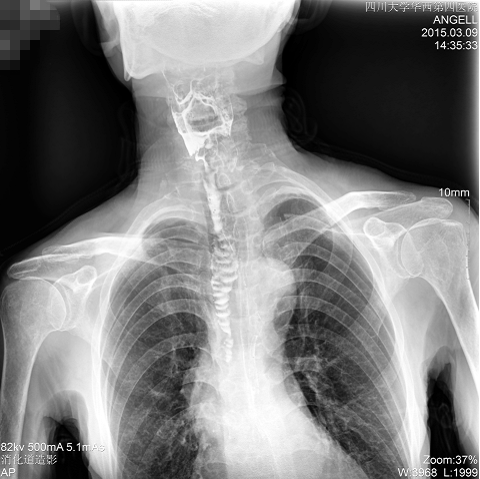

如下圖所示:該患者因吞咽時感到很難受,進食時也經(jīng)??人怨示歪t(yī)診斷。使用多功能dr為病人進行消化道造影診斷,要求他吞鋇后發(fā)現(xiàn),食道各段通過順利,形態(tài)規(guī)則,雙側(cè)梨狀窩不對稱左側(cè)稍淺,多次吞咽動作后,仍見鋇劑滯留,并見鋇劑進入氣管,屬于會厭征陽性。會厭功能紊亂,鋇劑進入了氣管。

圖為正位:通過動態(tài)影像可以清楚看到鋇劑進入了支氣管道且雙側(cè)梨狀窩不對稱

通過多功能dr可以診斷該病人的癥狀為會厭功能紊亂,鋇劑進入到了氣管。而在動態(tài)透視下可以清晰的觀察到鋇劑從何處進入氣管,可清晰顯示食管粘膜結(jié)構(gòu)。使用多功能dr其獨特的視頻采集技術(shù),可實時保存視頻并能實現(xiàn)900萬像素實時點片,才能獲取這樣清晰的病灶點。而常規(guī)dr只能拍攝靜態(tài)片,且成像效果大打折扣,因此較難確診病灶。